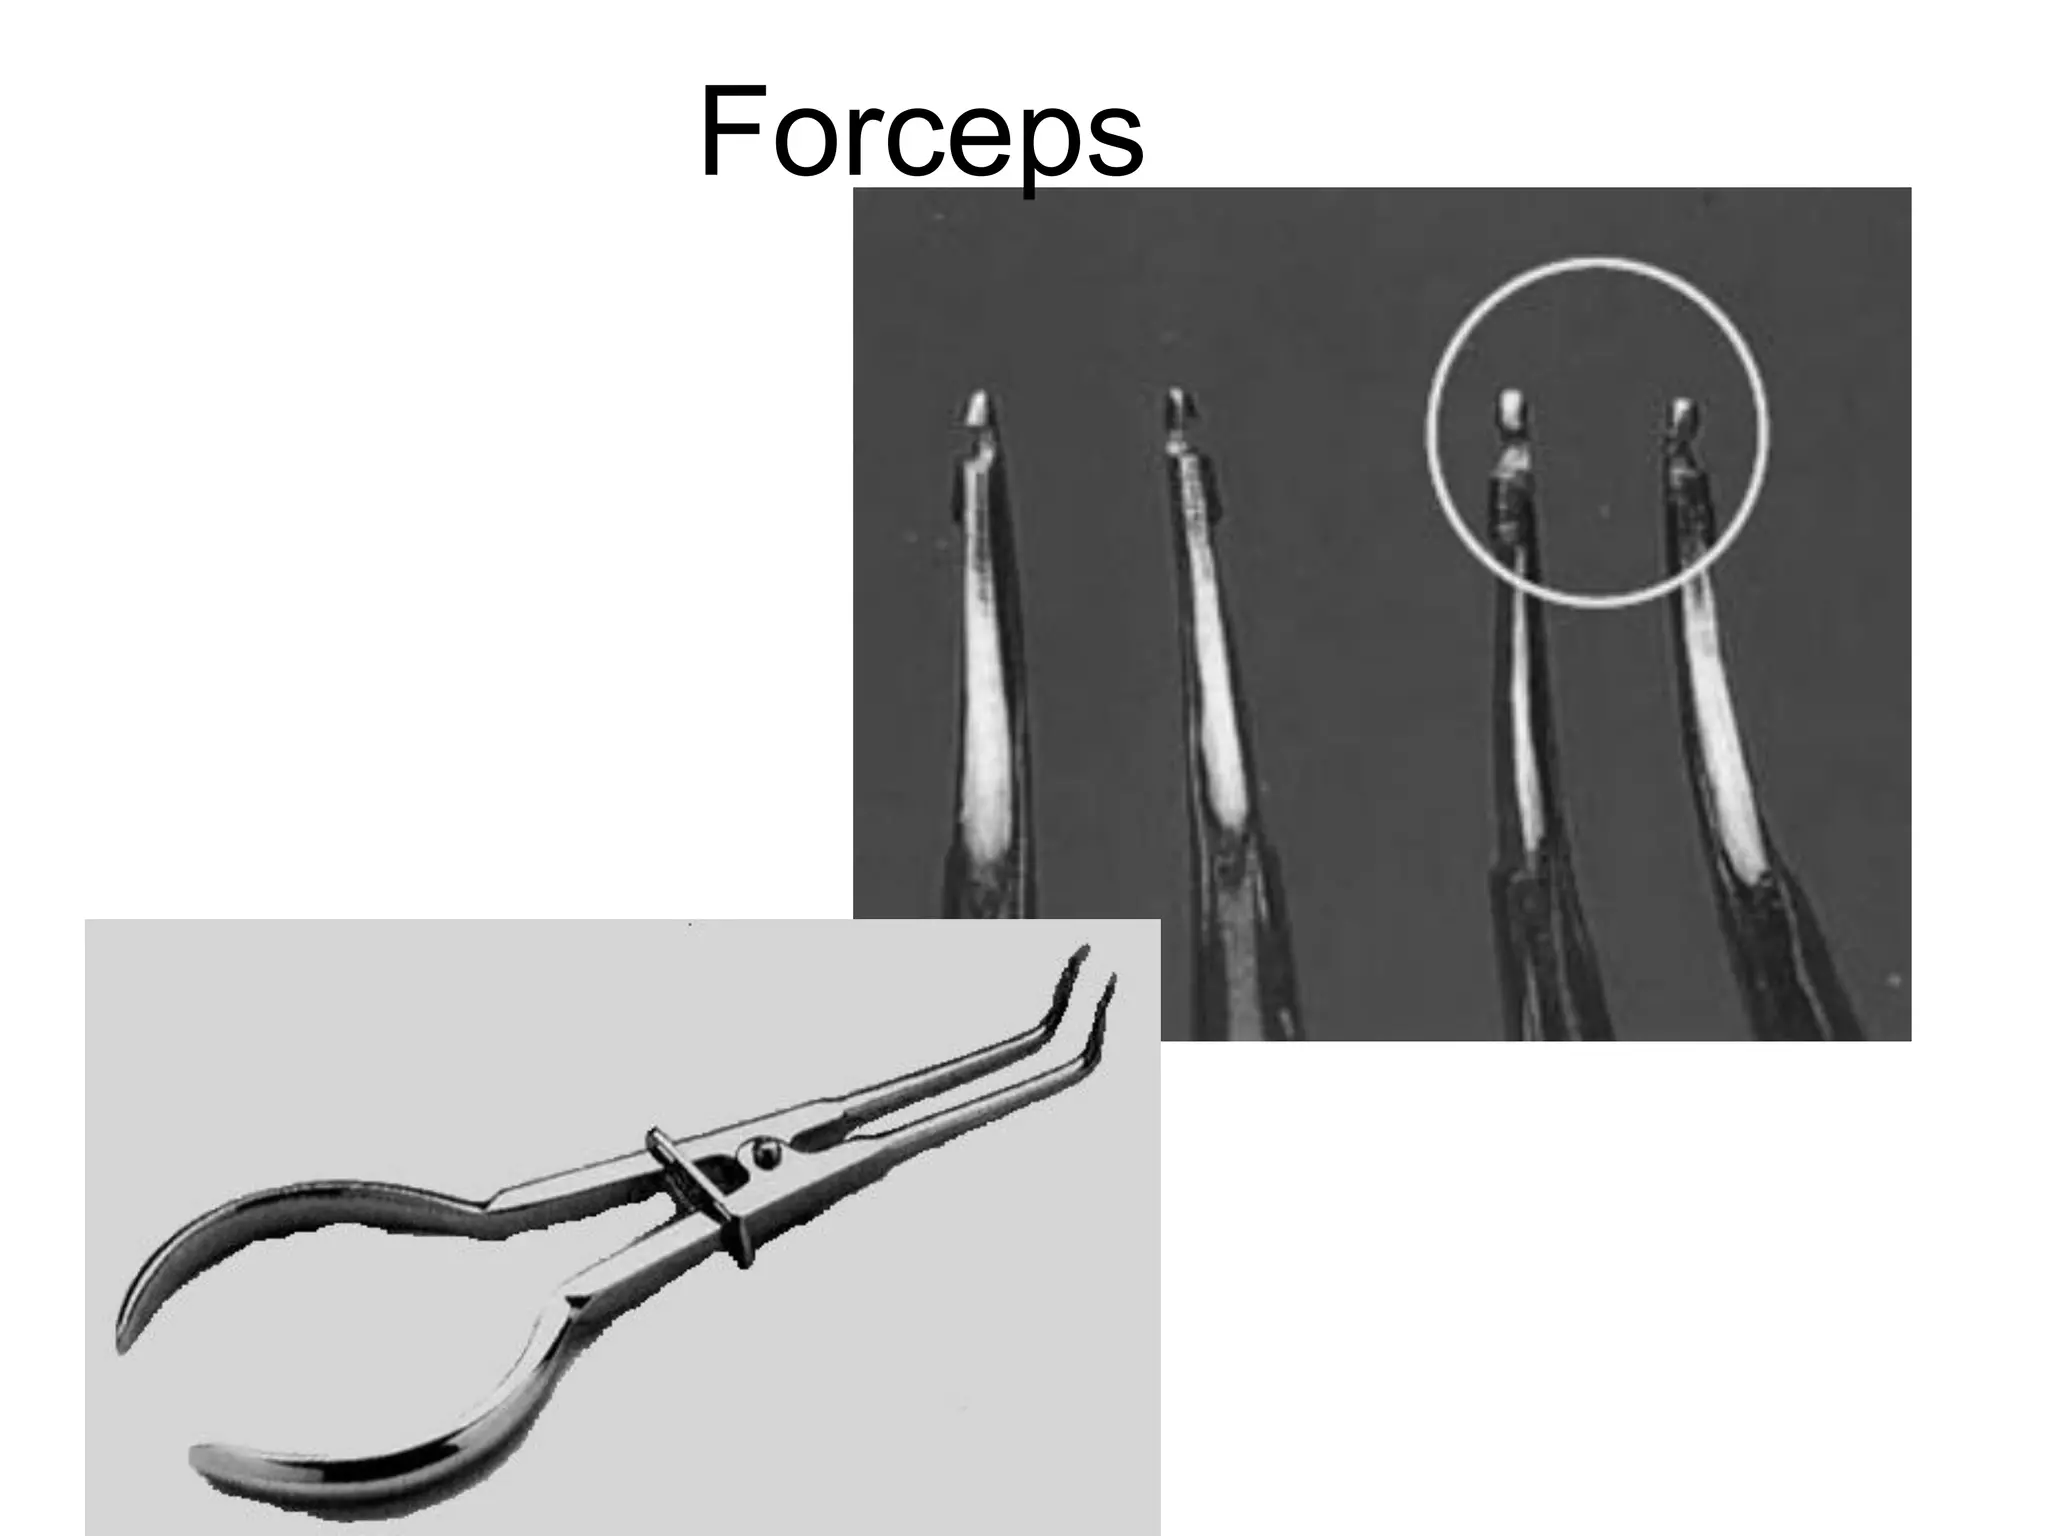

This document discusses the materials and components used for rubber dam isolation in dentistry. It describes the different types of rubber dam materials including color options and napkins to absorb moisture. It also outlines the tools needed such as punches to make holes, templates and stamps to guide hole placement, clamps to secure the dam, and other accessories like wedges and lubricant. Finally, it provides guidance on punching holes for different types of teeth and properly placing clamps in the rubber dam.